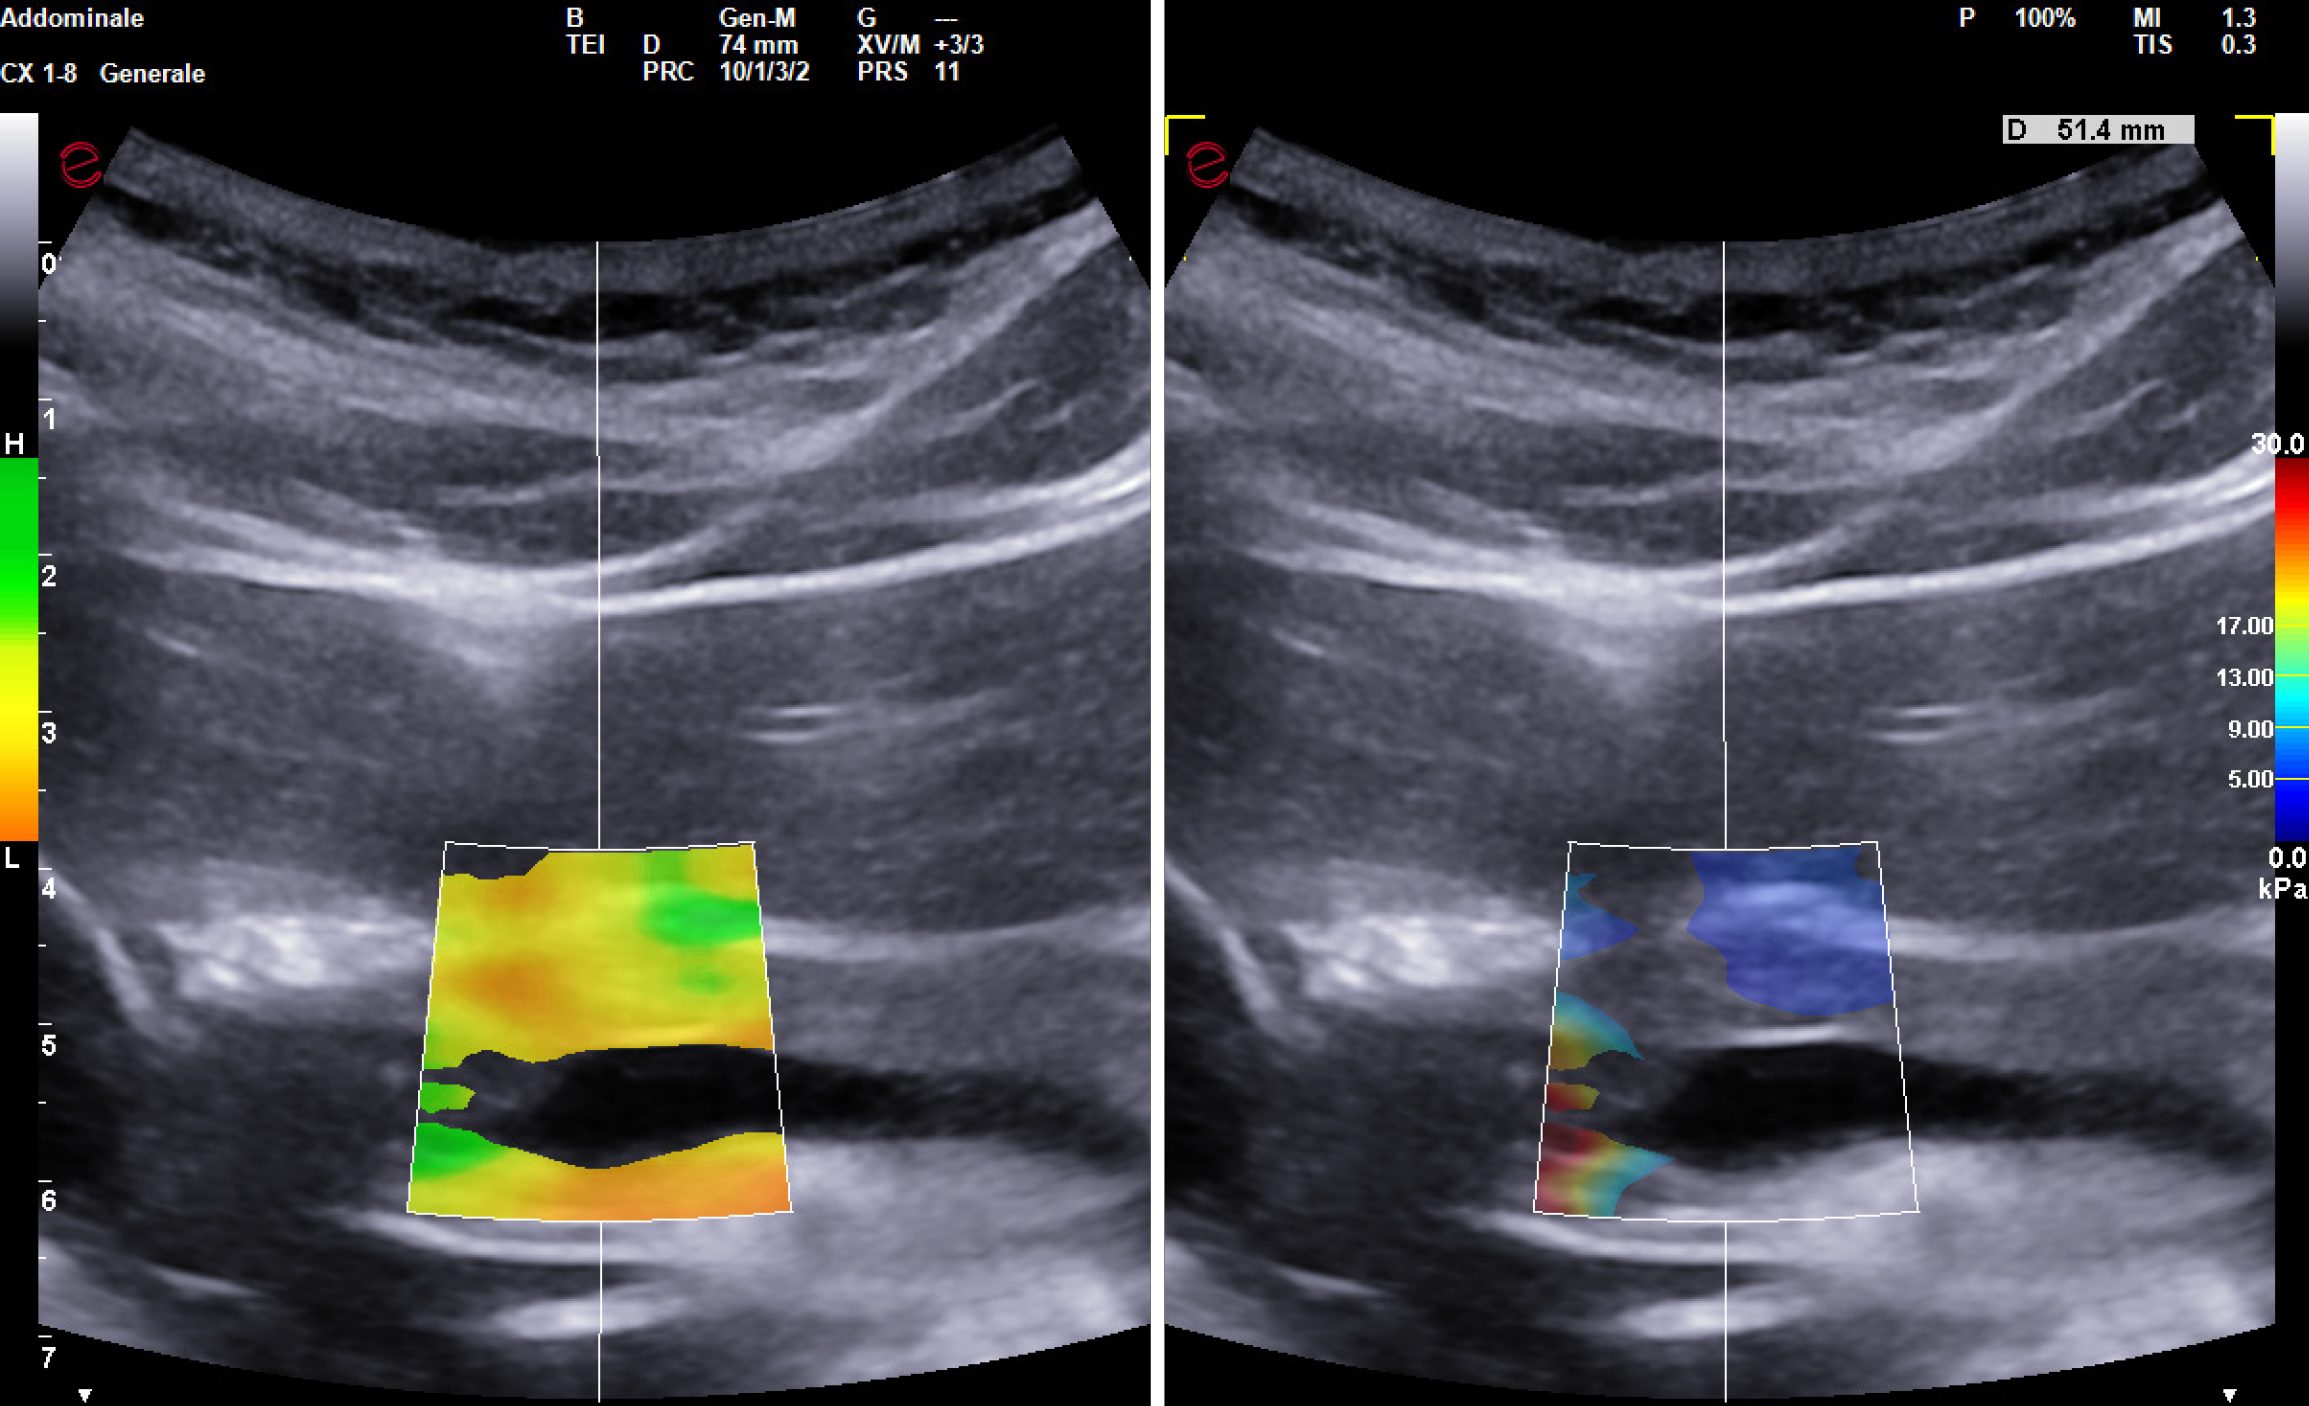

Figure 1 Shear wave elastography in healthy patients.

A-C: Point-shear wave elastography of liver (A), spleen (B), and pancreas (C); D-F: 2-dimensional-shear wave elastography of liver (D), spleen (E), and pancreas (F); G-I: 2-dimensional-SuperSonic Imagine Aixplorer of liver (G), spleen (H), and pancreas (I).